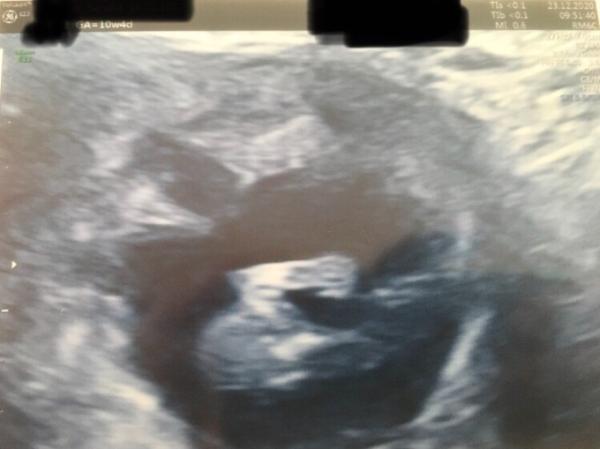

Hallo zusammen, heute war es nun auch bei mir soweit- erster Termin bei 10+4 . Mein Mann durfte dabei sein und die FÄ war zufrieden. Alles so, wie es sein soll. Baby war sehr aktiv, so dass es keine schönen Bilder gab. Aber immerhin einen winkenden Arm, als wollte es „Hallo“ sagen . ET 17.07.2021 LG

Bild zu zurück von FÄ - Forum für Juli - Mamis